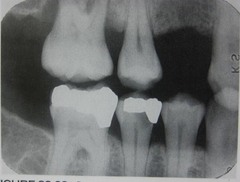

poorly contoured crowns

Front

Back